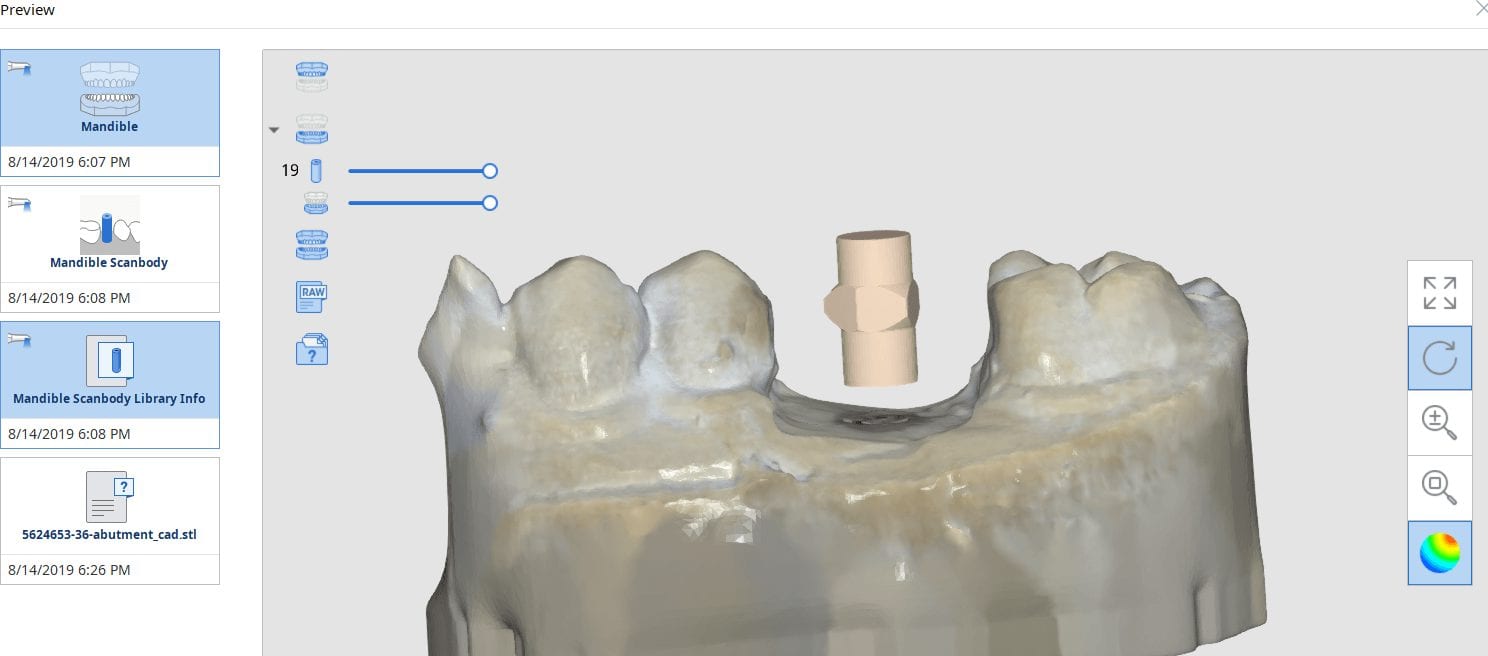

August 15, 2019In this article, we feature an upper left lateral crown that needed to be replaced due to recurrent decay. While the patient was getting numb, we defined the job description […]